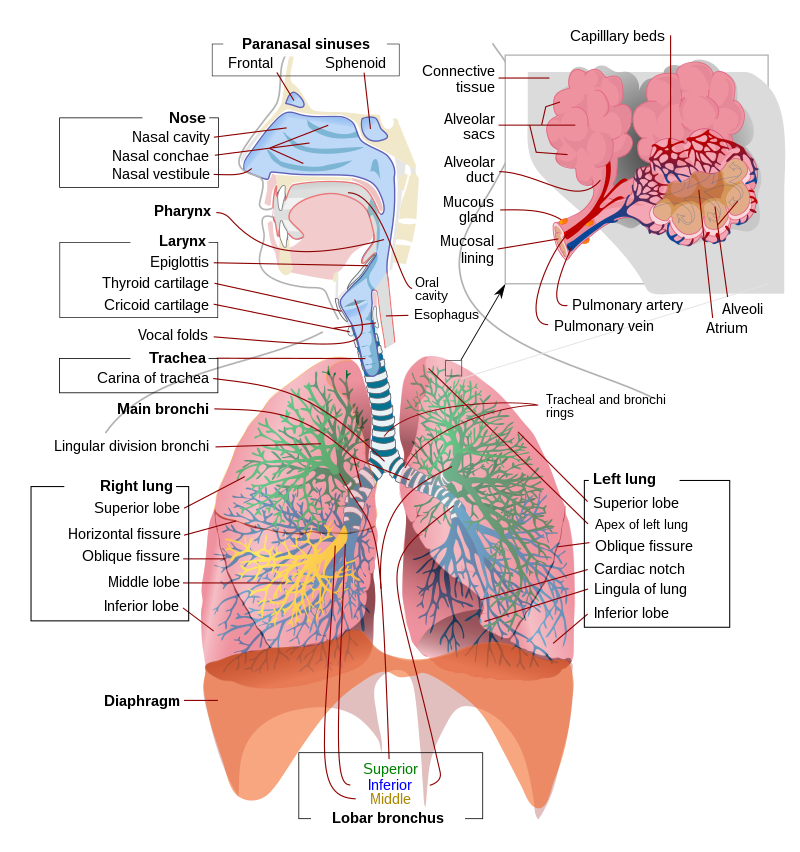

Respirologists, sometimes referred to as pulmonologists, are medical doctors who further specialize in the diagnosis and treatment of lung disease, such as asthma, emphysema, or pneumonia. Respirologists perform tests to check how well a person is breathing. Arca Clinic DR.VISWWAMBHAR one of the best Respiratory Specialist near by Pudupakkam.